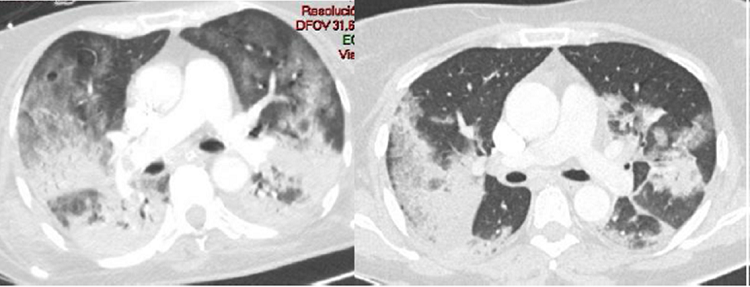

Todos los pacientes de la serie tenían hipoxia y aumento de las cifras de Dímero D con normalización en la cifra de otros parámetros típicamente alterados en esta enfermedad. De los ocho pacientes con TEP solo en dos había afectación múltiple y en ramas principales y lobares (Figura 1). En uno de los dos casos días después se confirmó la existencia de una extensa trombosis de las venas iliacas y femoral derecha como causa del TEP (Figura 2). En los otros seis casos el trombo era único y en ramas de pequeño calibre (Figura 3). En uno de los pacientes el trombo afectaba a la vena pulmonar superior izqda (Figura 4).

En la mayoría de los casos en que se vio enfermedad tromboembólica la enfermedad pulmonar era grave desde el punto de vista de la imagen,seis casos (Figura 5), en otro era moderado-grave y en un tercer paciente no había evidencia de afectación pulmonar, el paciente estaba diagnosticado de silicosis pulmonar (Figura 6) y tenía antecedentes de una neoplasia de páncreas irresecable a tratamiento con quimioterapia con fiebre y PCR positiva para COVID-19. Cuatro de los 8 pacientes con TEP tenían enfermedad muy evolucionada y grave con respiración asistida e ingreso en la UCI. Todos los pacientes tenían adenopatías mediastínicas lo que podría traducir un estado de gran inflamación (Figura 7) que podría explicar la cifra alta de Dímero D en los casos en que no existía enfermedad tromboembólica.